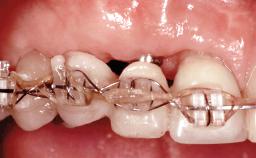

Replacement of an Upper Right Central and Lateral Incisor with an Implant-Supported Crown and a Distal Cantilever

This 20-year-old woman was referred to our department in July 2006. Four months earlier, she had experienced dental trauma to the anterior maxilla when traveling in South America. The emergency treatment included emergency root canal treatment of teeth 12 and 11. Tooth 21 was also subjected to endodontic treatment later. At the initial examination, the patient was not in pain but reported increased mobility of tooth 12. The clinical examination revealed a high smile line, medium thickness of the soft tissue, and rectangular tooth forms. Discoloration of tooth 12 was evident. The periapical radiograph provided by the referring dentist indicated a fracture line at both teeth 12 and 11. A cone-beam computed tomography (CBCT) scan confirmed these fractures. No pathology was found to be associated with tooth 21.